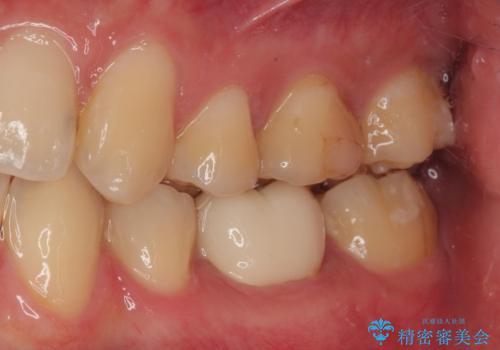

虫歯による不快な症状がなくなり喜んでいただきました。セラミックの被せものが入った後の違和感なく過ごせているそうです。矯正治療終了直後の被せもの治療なのでリテーナーの作成回数をできるだけ少なく迅速に行うことを考慮して治療を行いました。

今後、ホワイトニングを行う予定なので、患者様のご希望により、周りの歯に比べてあえて白い被せものを作成しました。